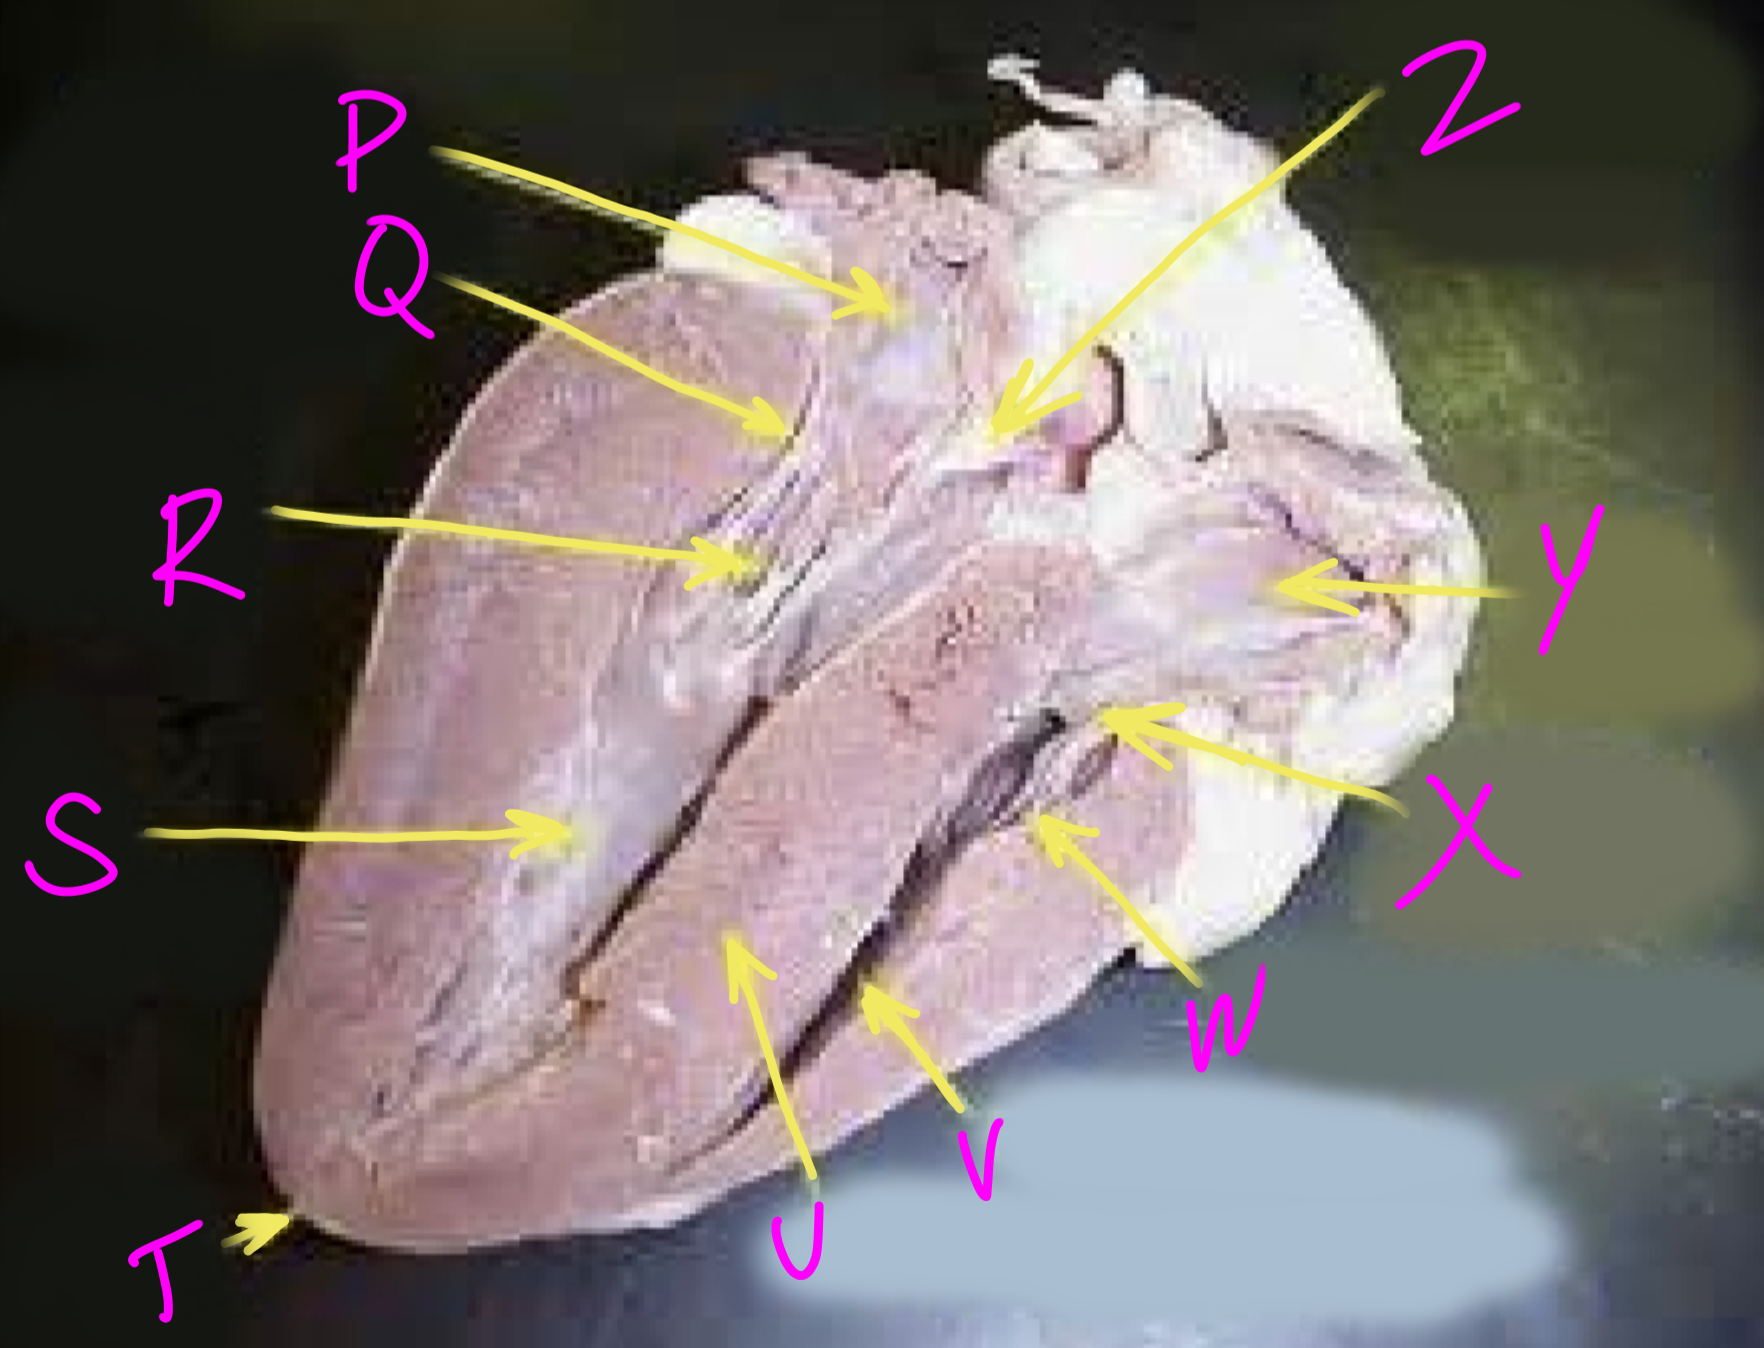

P

Left atrium

Q

Bicuspid valve - allows blood to flow from the left ventricle to the aorta

R

Right chordae tendinae - hold AV valves in place

S

Left ventricle

T

Apex - pumps blood out of the ventricles

U

Interventricular septum - divides the right and left ventricles

V

Right ventricle

W

Left chordae tendinae - hold AV valves in place

X

Tricuspid valve

Y

Right atrium

Z

Aortic semilunar valve - prevent backflow